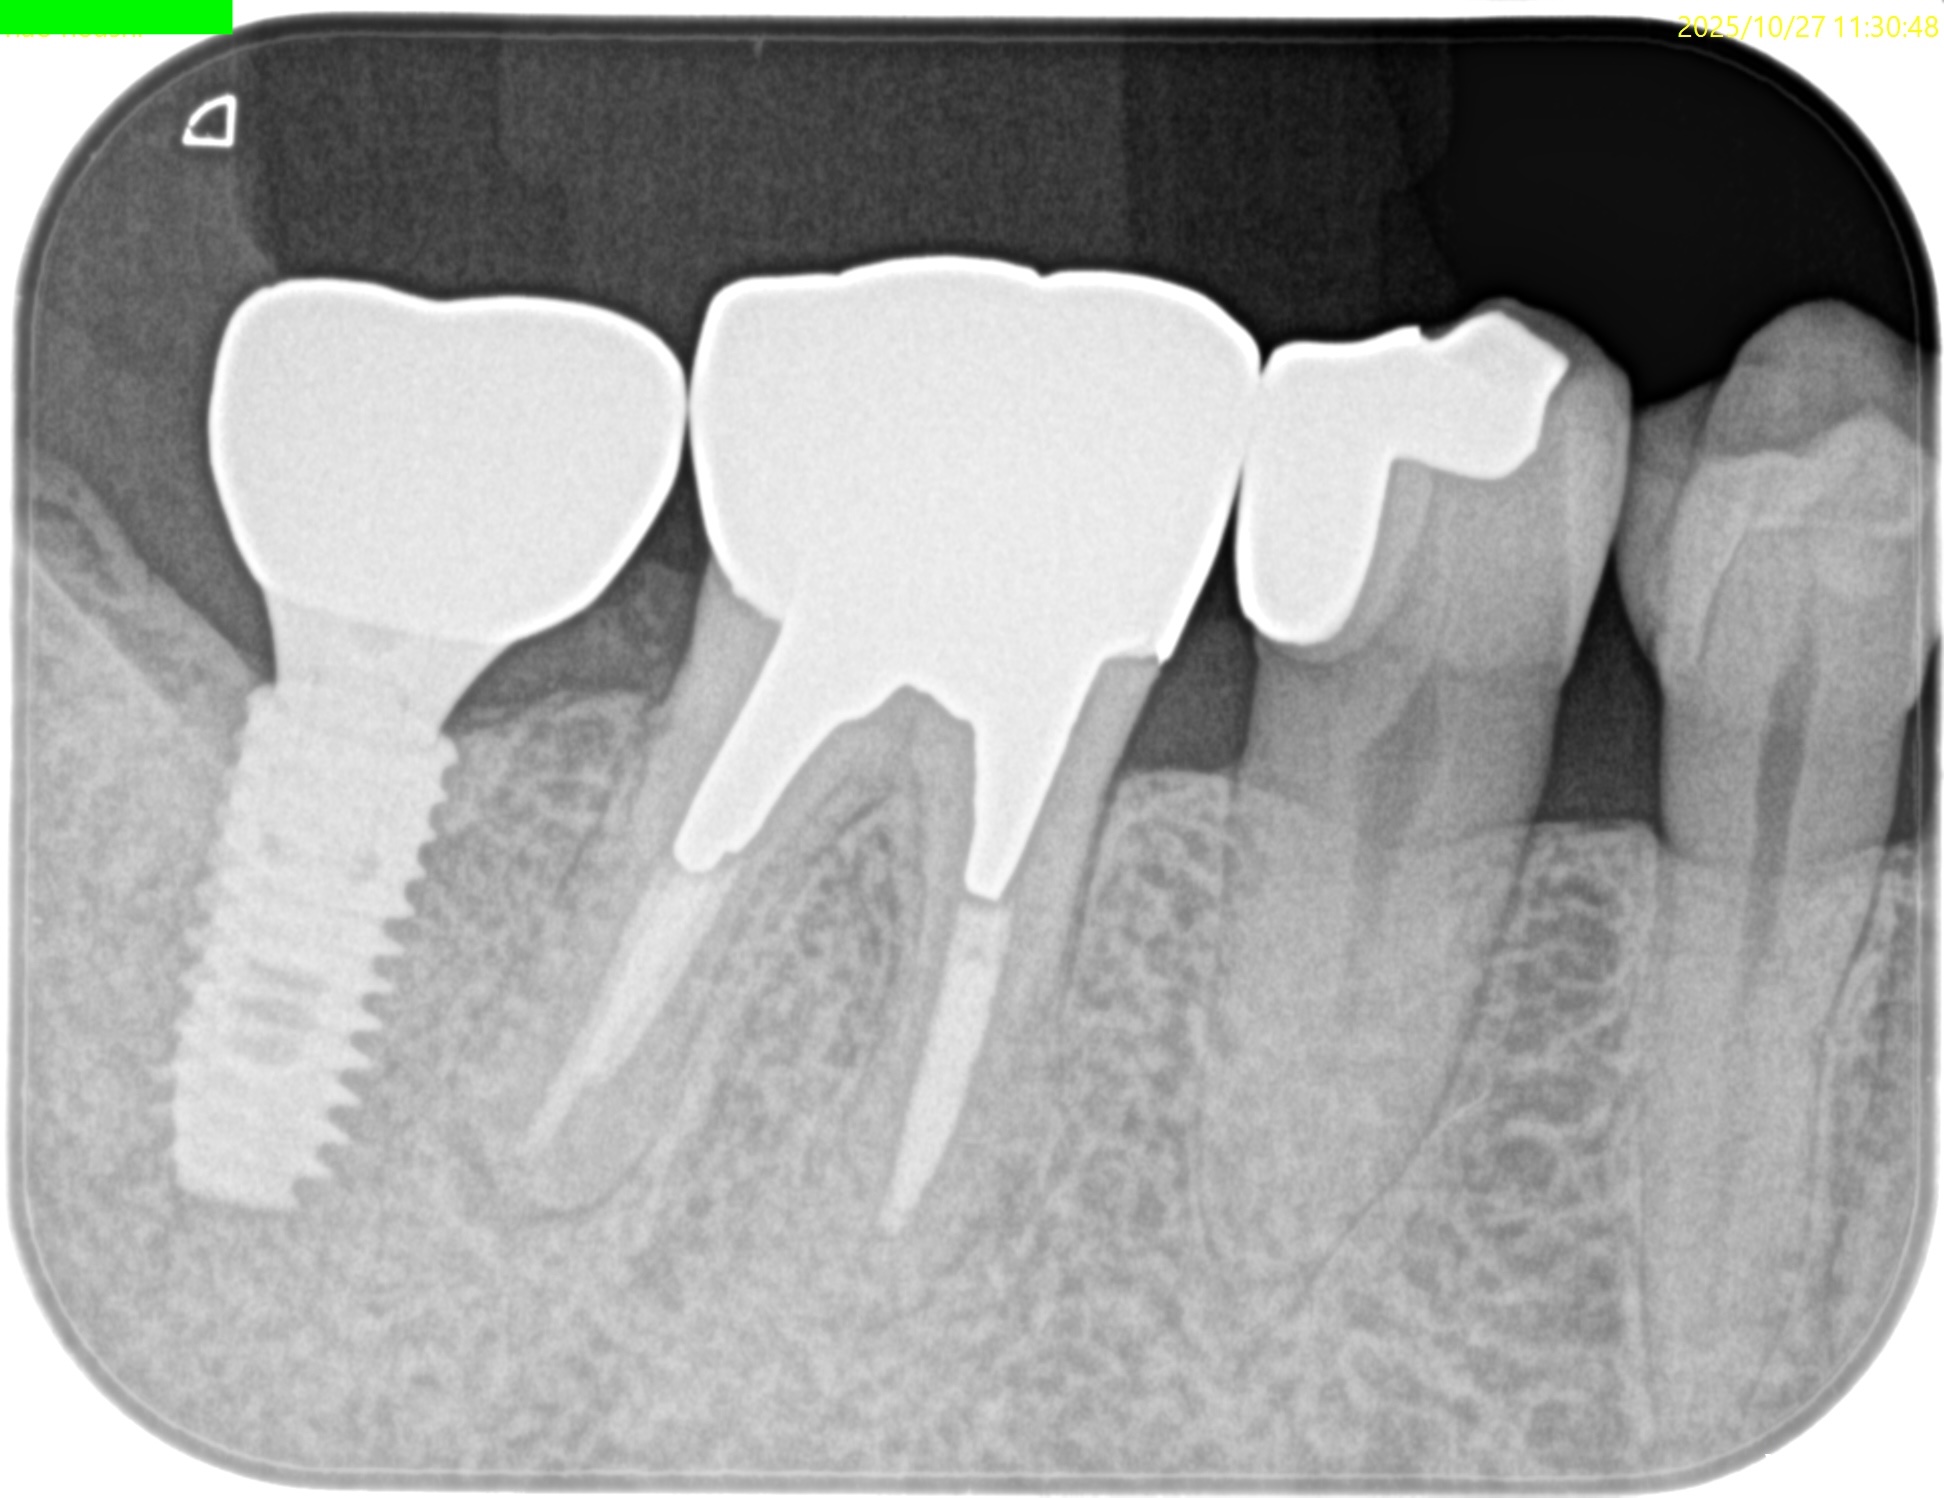

PA(2025.10.27)

近心はテーパー型、

遠心はパラレルで外れにくい感じのメタルポストコアだ。